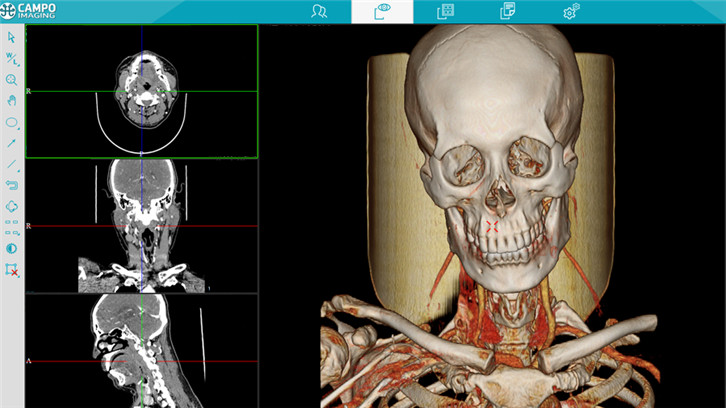

图像浏览

三维图像重建

多平面重建